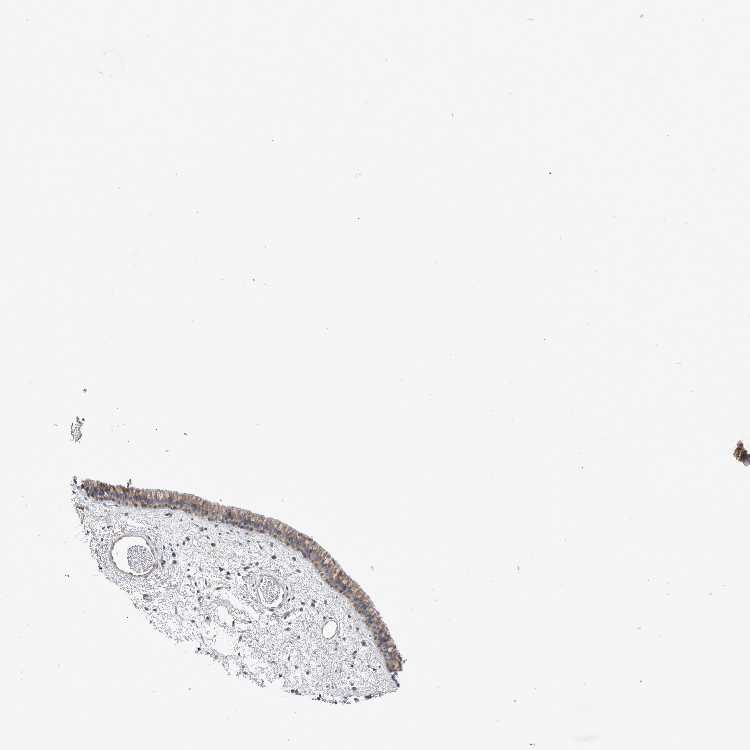

NASOPHARYNX - Antibody stainingi

Antibody staining in the annotated cell types in the current human tissue is reported as not detected, low, medium, or high, based on conventional immunohistochemistry profiling in selected tissues. This score is based on the combination of the staining intensity and fraction of stained cells.

Each image is clickable and will lead to virtual microscopy that enables deeper exploration of all samples and also displays staining intensity scores, fraction scores and subcellular localization as well as patient and tissue information for each sample.

Antibody HPA027006

Respiratory epithelial cells Medium